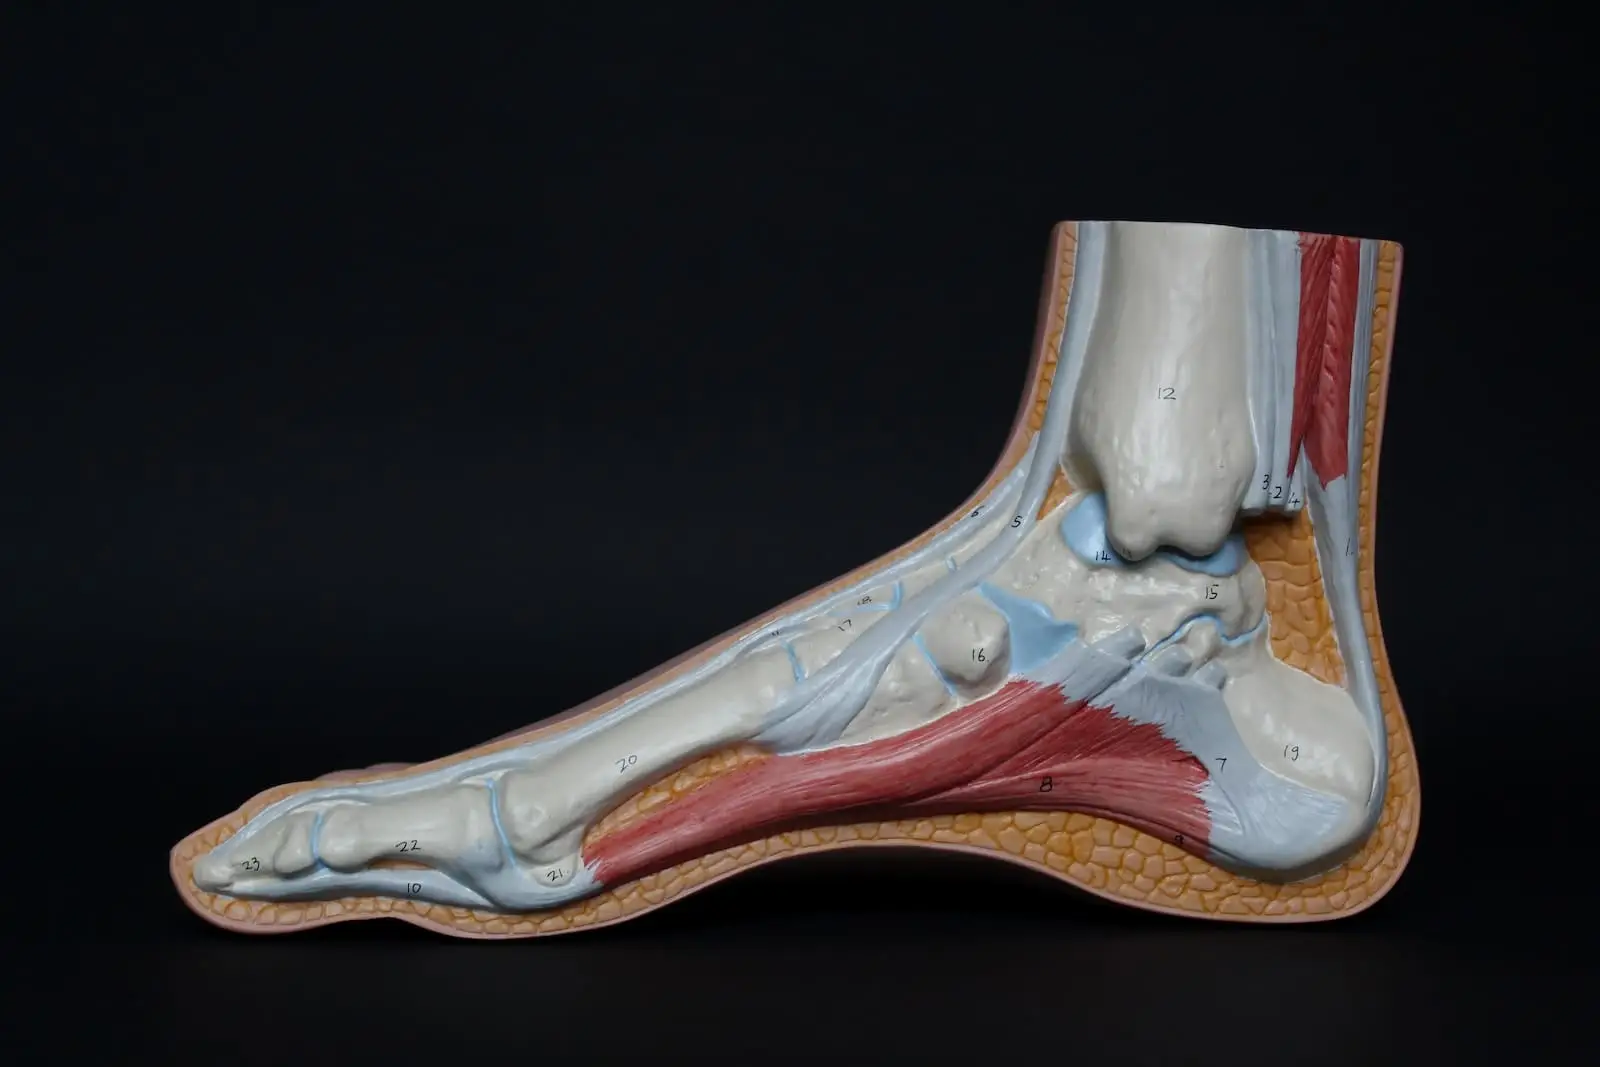

ACHILLES TENDON

ANKLE INJURY

ANKLE SPRAINS

FOOT